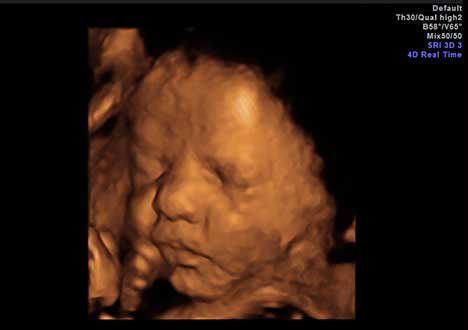

• Acompanhar o desenvolvimento do feto na gestação com imagens 3D e 4D (gravação de vídeo);